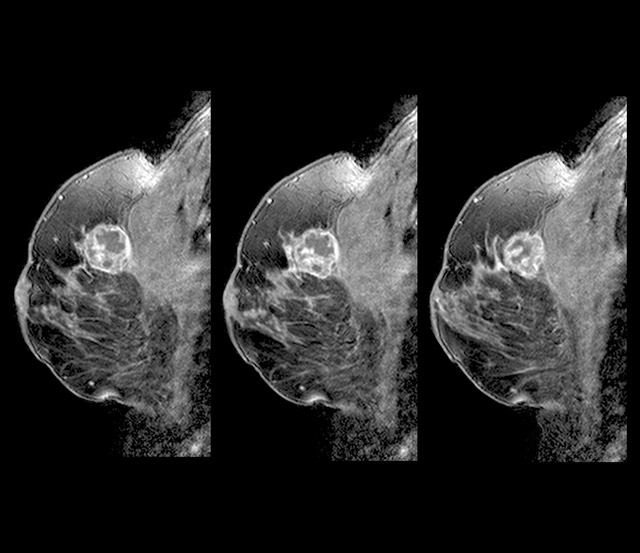

유방암 초기증상 - 덩어리 또는 멍울

유방암을 알아차리는 가장 일반적인 방법은 유방에 덩어리 또는 만져지는 덩어리가 만져지는 것입니다. 멍울은 이전에 본 적 없는 신비한 덩어리이며, 악성이라면 단단하고 고정되어 움직이지 않으며 모양이 불규칙합니다. 모든 멍울이 악성은 아니며 양성일 수도 있으므로 의사와 정기적으로 검진을 받는 것이 중요하므로 이러한 유방암 초기증상을 그냥 지나치지 마시기 바랍니다.

유방암 자가검진하기

유방암 자가 검진에는 육안 및 촉각 검진 방법이 있습니다. 전신 거울 앞에 서서 유방의 윤곽, 대칭, 움푹 들어간 곳이 있는지 확인합니다. 엄지와 약지를 제외한 가운데 세 손가락으로 유방의 덩어리나 피부 변화를 만져봅니다. 유두에서 비정상적인 분비물이 나오는지, 겨드랑이에서 덩어리가 만져지는지 확인할 수도 있습니다.